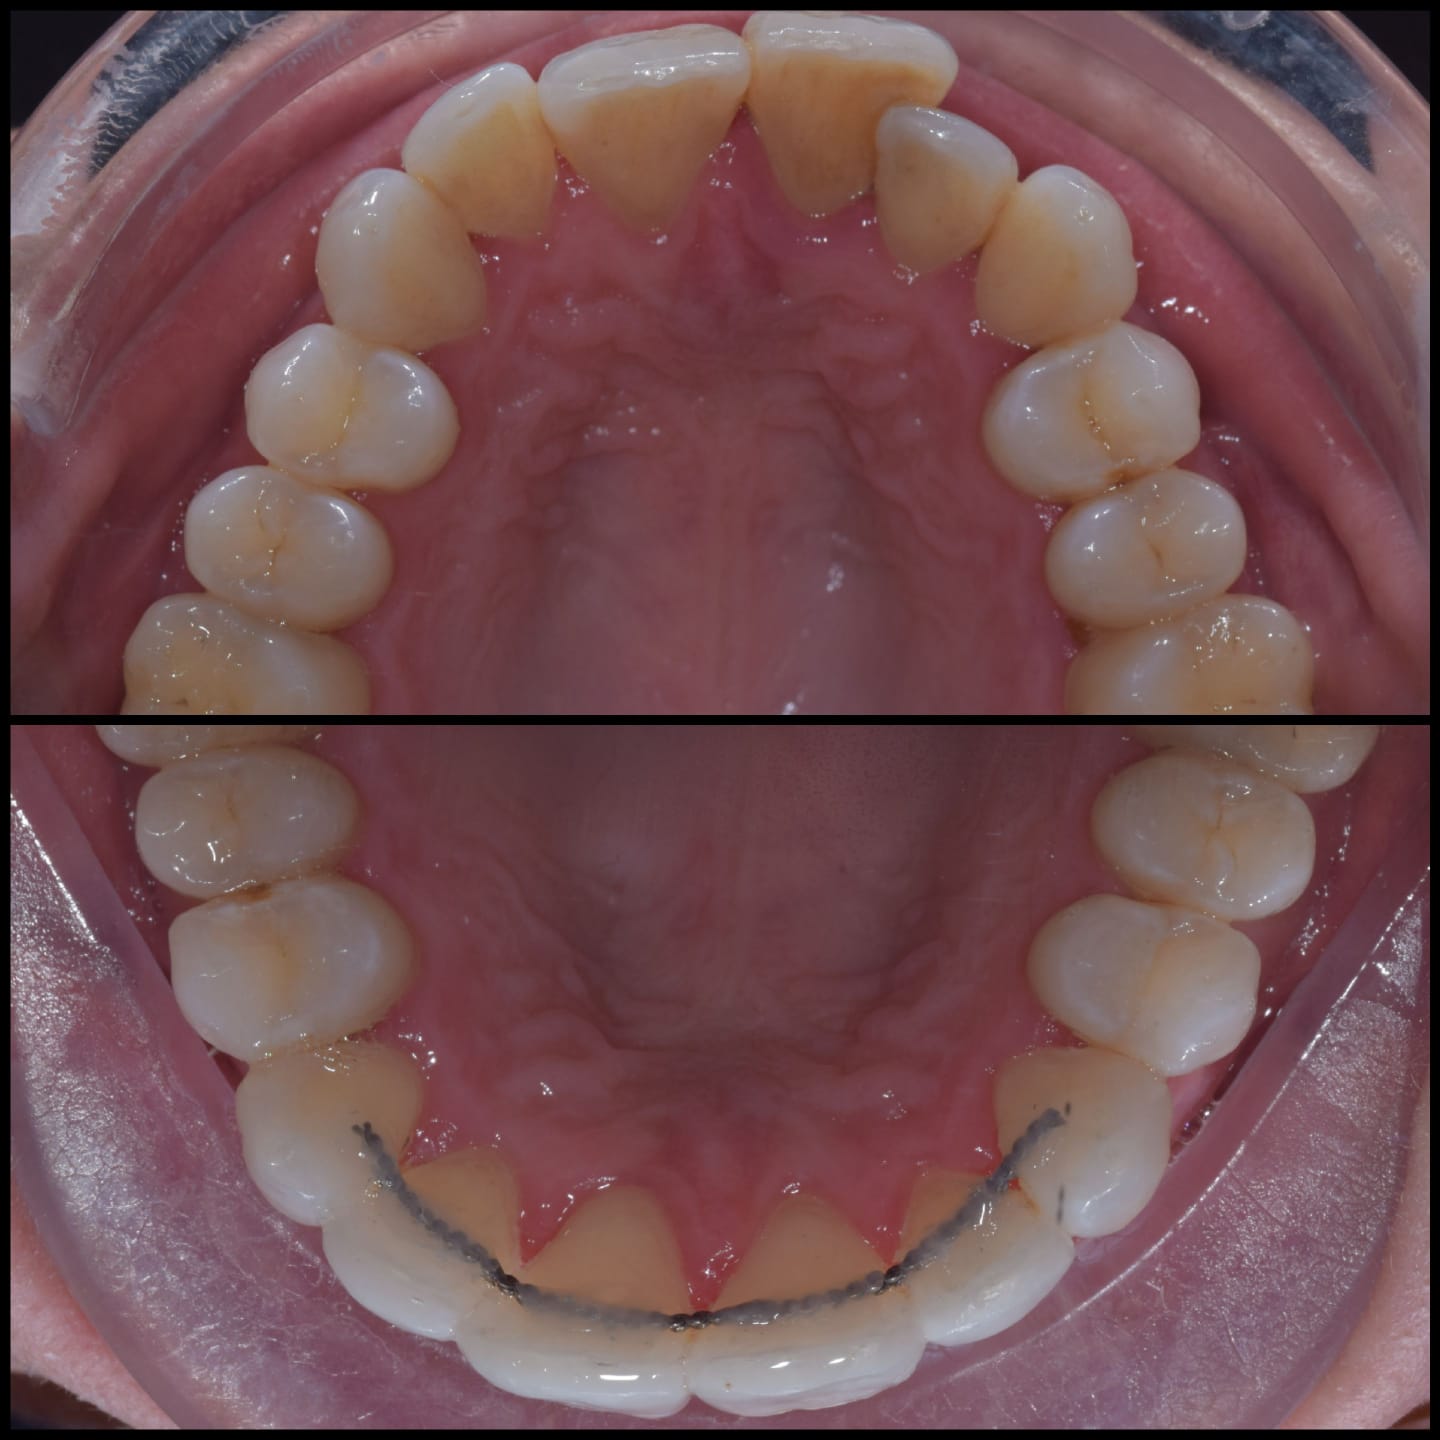

Invisalign is a well-known system for straightening teeth in the most discreet way. It works by using a series of clear aligners that fit comfortably over the teeth to gently move them into the desired position over time. There are no fixed brackets or wires used, in fact, the aligners are completely removable.

Virtually invisible way to straighten your teeth

Removable aligners make eating and dental care easy